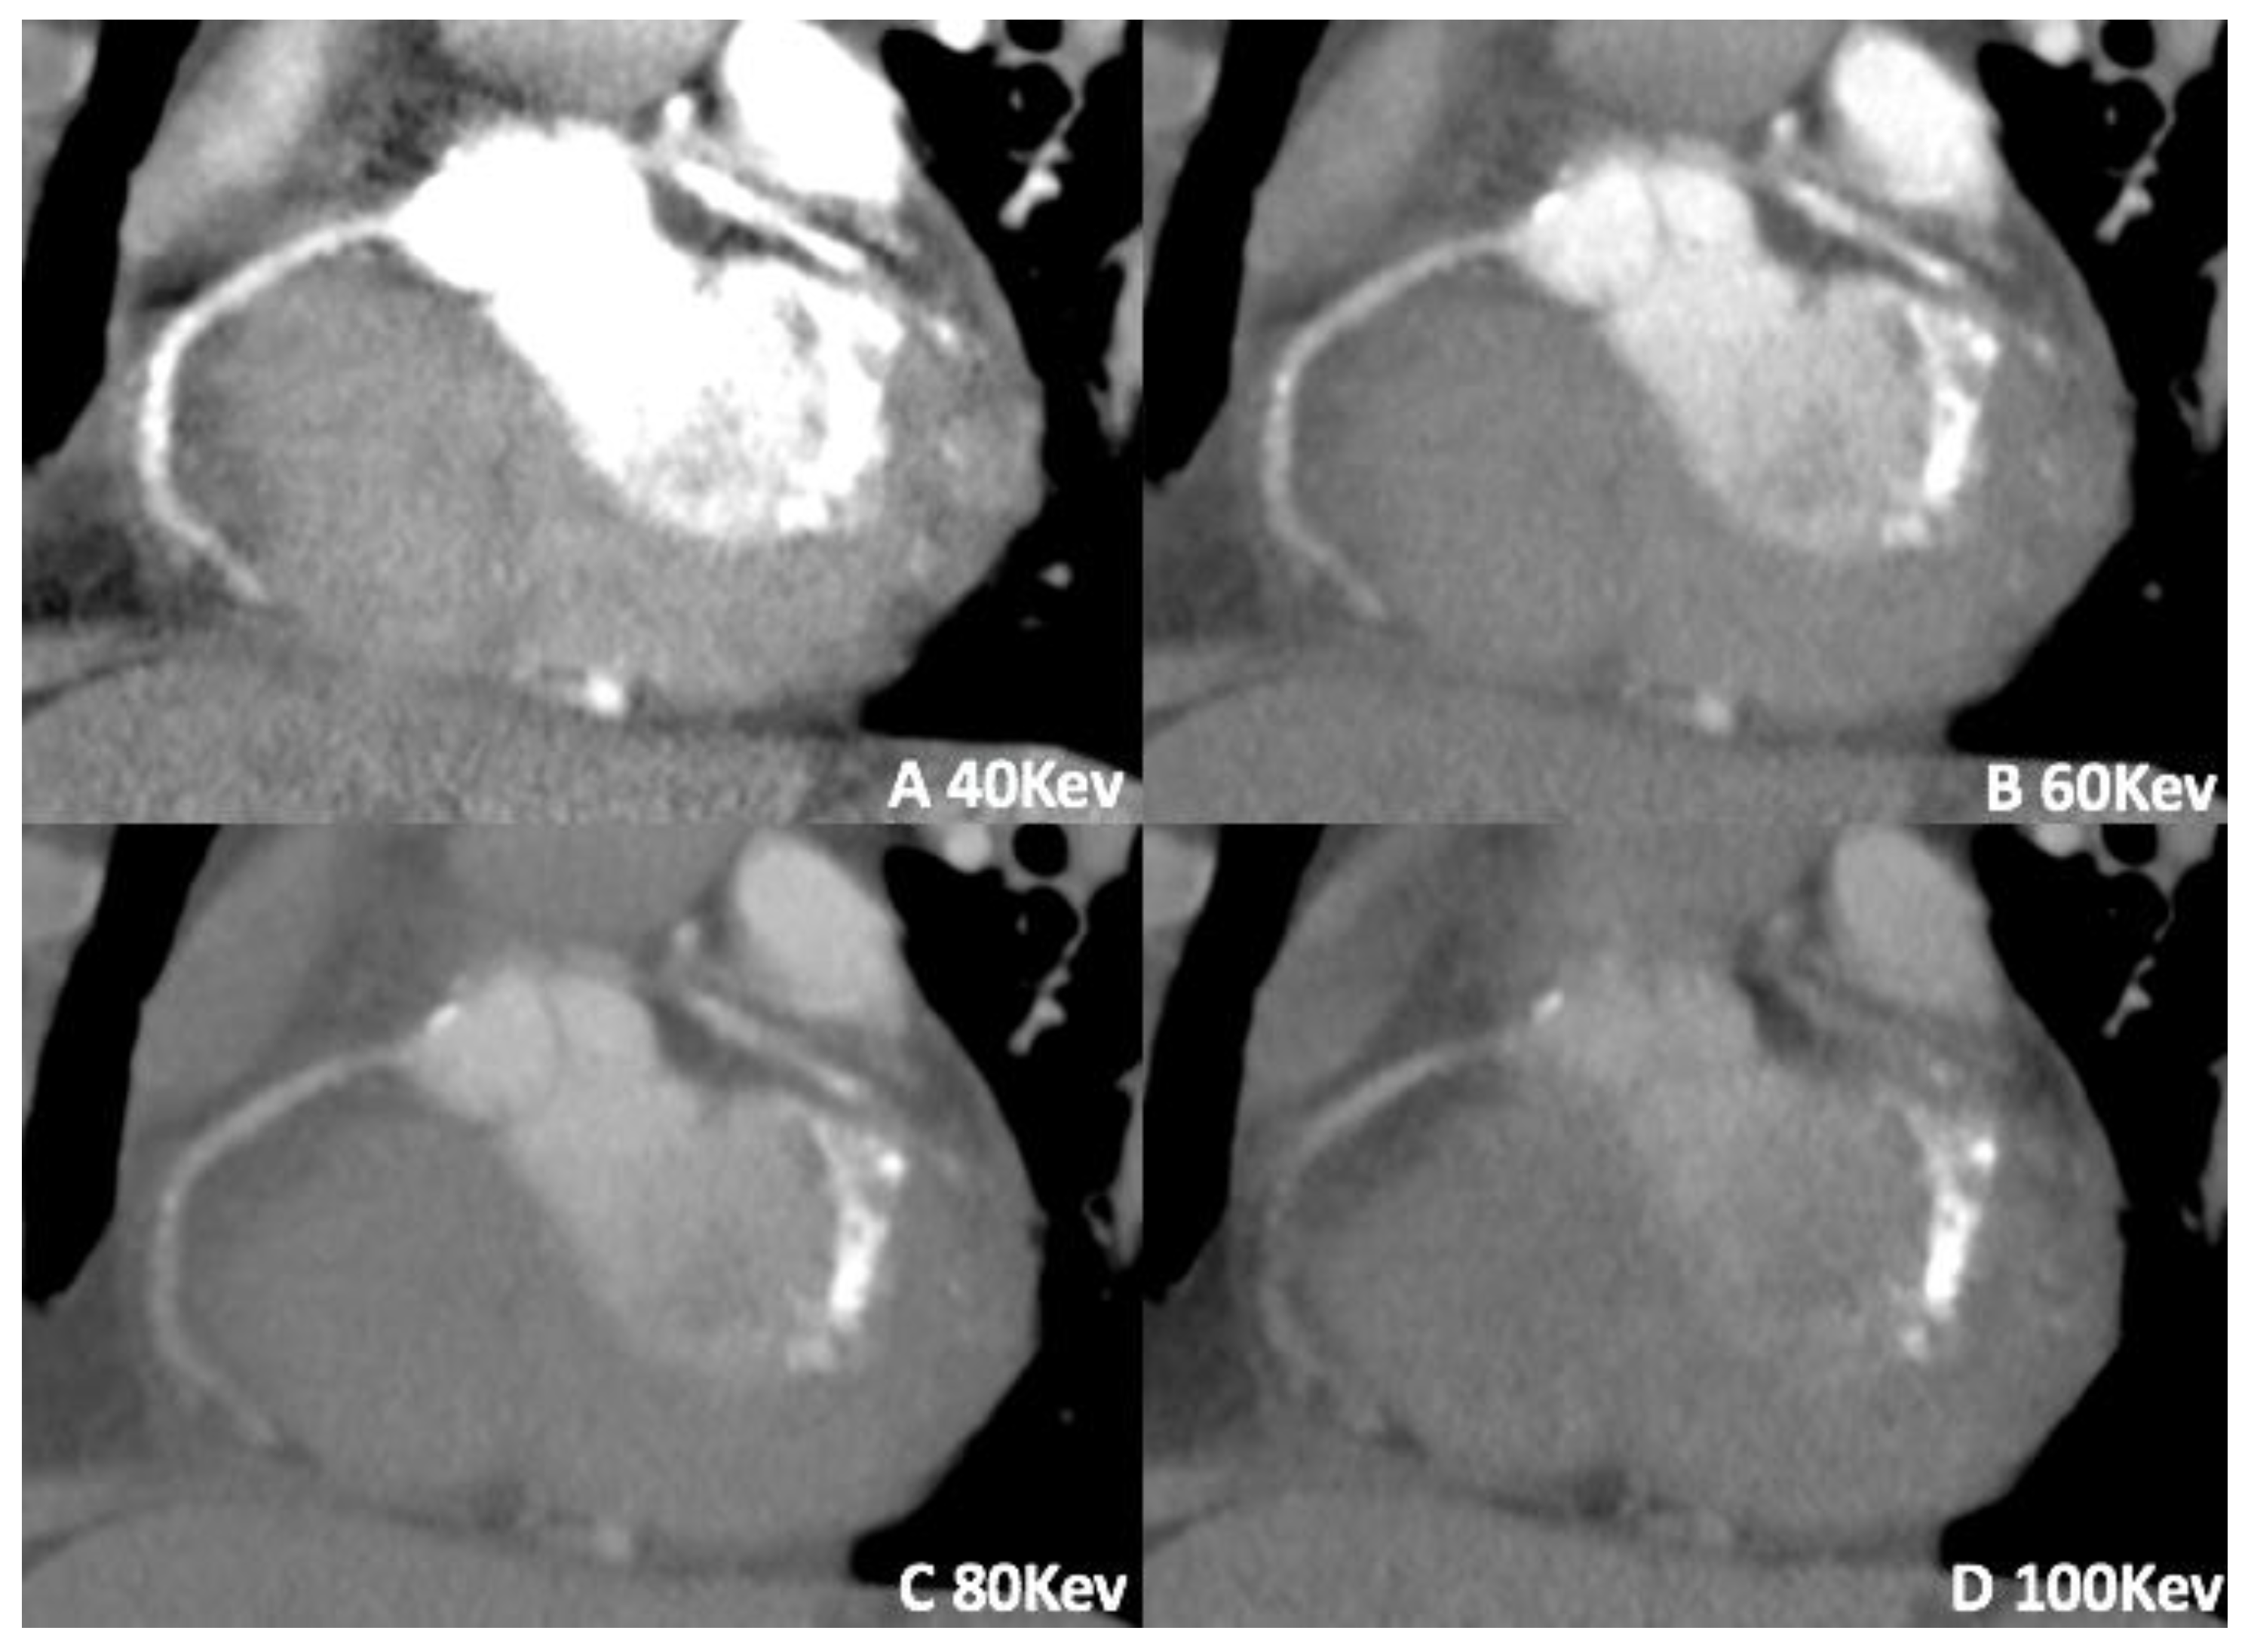

3.1. Virtual Monoenergetic Imaging (VMI)